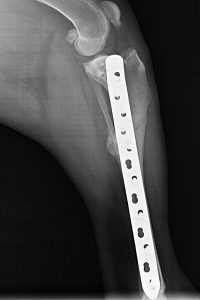

Golden Retriever Bella schien wie vom Pech verfolgt. 2016 zog sich die schöne Hündin im Abstand weniger Monate zwei Kreuzbandrisse zu, die in der Tierklinik Ismaning per TPLO chirurgisch versorgt wurden. Alles verheilte gut, und Bella konnte nach den entsprechenden Schonzeiten ihre Kniegelenke wieder voll belasten. Doch dann wurde sie im Januar 2018 von einem Auto angefahren, und ihr linker Unterschenkel brach genau unterhalb der Knochenplatte, die Bella im Rahmen der TPLO zur Knochenstabilisierung eingesetzt worden war (Röntgenbild ganz rechts). Bellas Frauchen befürchtete schon das Schlimmste. Doch unser Chefarzt Dr. Klaus Zahn konnte Bellas Beinchen wieder vollständig herstellen. Bei OP Nummer drei entfernte er die alte Platte und verschraubte eine neue im Knochen. Die Folge: Heute rennt, läuft und spielt Bella, als ob nie etwas gewesen wäre.